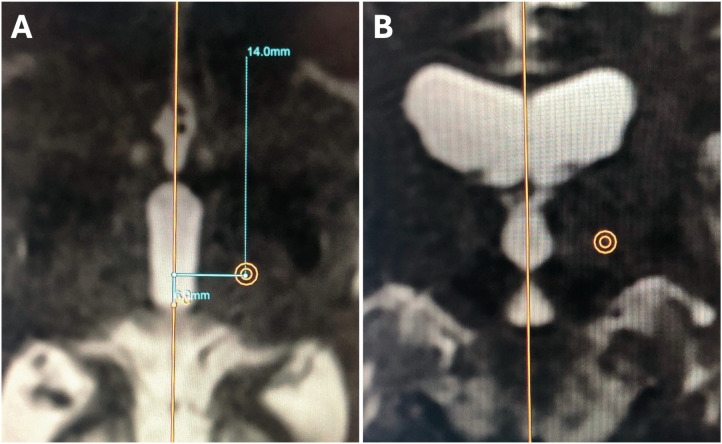

Material and methods: Preoperative and postoperative white matter null (WMn) MR-imaging was employed for direct Vim detection. Essential anatomical landmarks are identified. Dual-lesion conformality was used to adapt to the spatial distribution of the Vim.

Results: Lesions of the Vim were identifiable using the postoperative WMn MRI sequence. The direct visualization of the Vim usually avoids extension into the internal capsule and the sensory thalamic nucleus. Sagittal imaging confirmed the dual-lesion conformational strategy which conforms to the antero-superior orientation of the Vim.